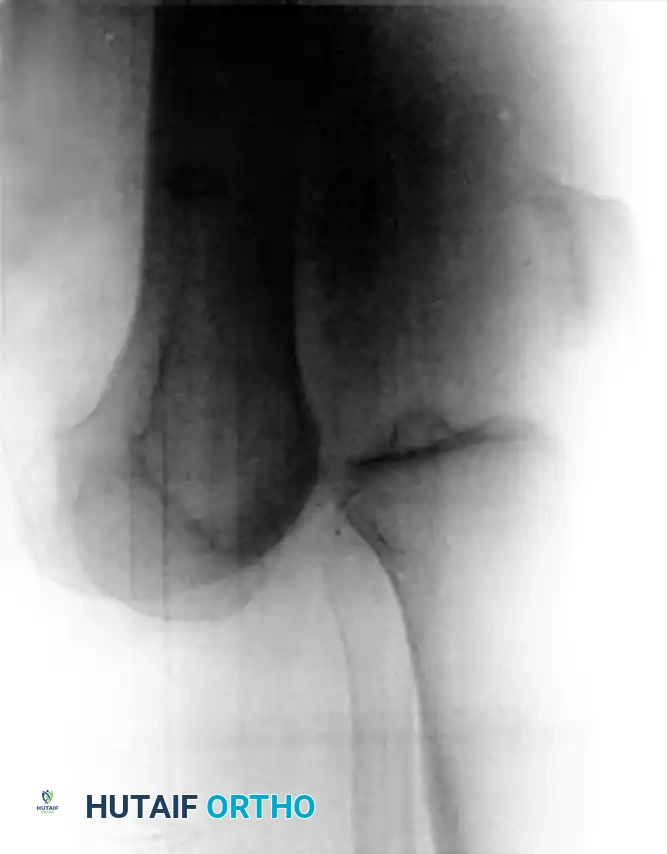

Figure 45-145: Anteroposterior (A) and Lateral (B) radiographs demonstrating an ultralow-velocity knee dislocation in a morbidly obese patient. Note the complete loss of tibiofemoral congruity.

Recent epidemiological shifts have highlighted a highly specific and dangerous subset of knee dislocations occurring in morbidly obese patients. These are termed ultralow-velocity knee dislocations. Unlike sports or motor vehicle trauma, these injuries occur during routine activities of daily living (ADLs), such as stepping off a curb, descending a single stair, or simply experiencing a mechanical fall while walking.

The biomechanical reality is that in a patient with extreme body mass, the kinetic energy generated by a simple ground-level fall is sufficient to completely rupture the multiligamentous complexes of the knee.